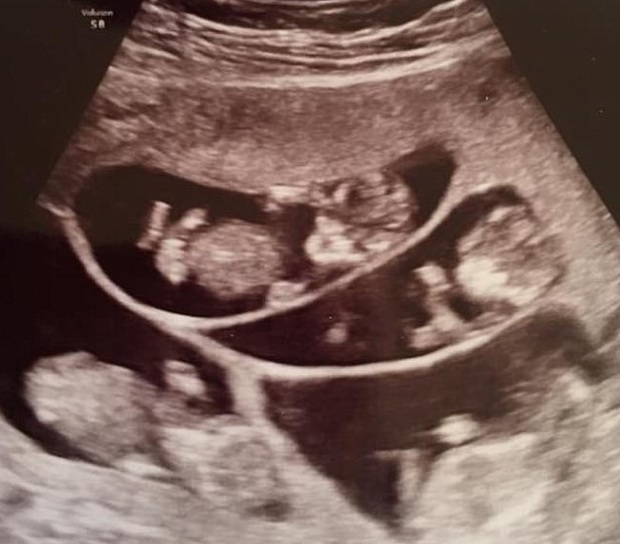

Hình ảnh siêu âm thai 7 của Bobbi

Khi em bé Mikayla lớn hơn một chút, cặp vợ chồng này quyết định chưa dừng lại và sẽ thử tìm cách để có thêm một đứa con nữa. Tại bệnh viện thai sản, họ được các bác sĩ gợi ý nên dùng Metrodin – một loại thuốc kích thích rụng trứng giúp phụ nữ mang thai. Bobbi sau đó thành công mang bầu em bé thứ hai. Cứ thế cặp vợ chồng đều đặn đến viện thăm khám để đảm bảo sức khoẻ cho cả hai mẹ con. Rồi ngày định mệnh ấy cũng đến, hôm đó, cặp vợ chồng có mặt để siêu âm như thường lệ thì bác sĩ thông báo trong bụng Bobbi không phải có một phôi thai mà có tận… 7 cái.